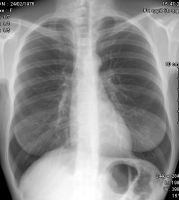

Qu'est ce qu'une radiographie ?

En quoi consiste l'examen ?

Une technique d'imagerie bien connue, et qui pourtant a aussi bénéficié de belles avancées technlogiques pour améliorer la qualité de l'image tout en baissant la dose de rayonnement, et en facilitant le travail des manipulateurs(trices).

• Principe

La technique utilise les rayons X, afin d'obtenir une projection  de la surface à radiographier.

La radiographie peut apporter une somme d'informations importantes

aux radiologues.Elle fait partie du bilan d'imagerie standard à réaliser, et va notamment apporter des informations sur la statique du patient ( images en station verticale), ce que l'imagerie en coupe ne permet pas.